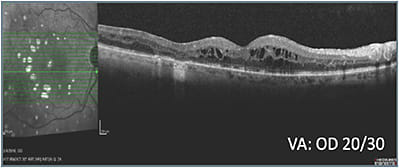

A series of treatments, during the course of which vision ranged from 20/50 to 20/25, failed to resolve the macular edema (B). With vision in the right eye consistently worse than in the left eye and worsening, and the patient experiencing hardship remaining away from home for treatment, an alternative class of therapy was initiated and led to improved retinal anatomy (C, D, & E). Intraocular pressure (IOP) increased to 25 mm Hg and was observed without treatment. When pressure increased to 28 mm Hg, the patient was started on a topical IOP-lowering drop, which lowered the pressure to 19 mm Hg. The right eye has remained fluid free on the alternative class of therapy and a single IOP-lowering agent.